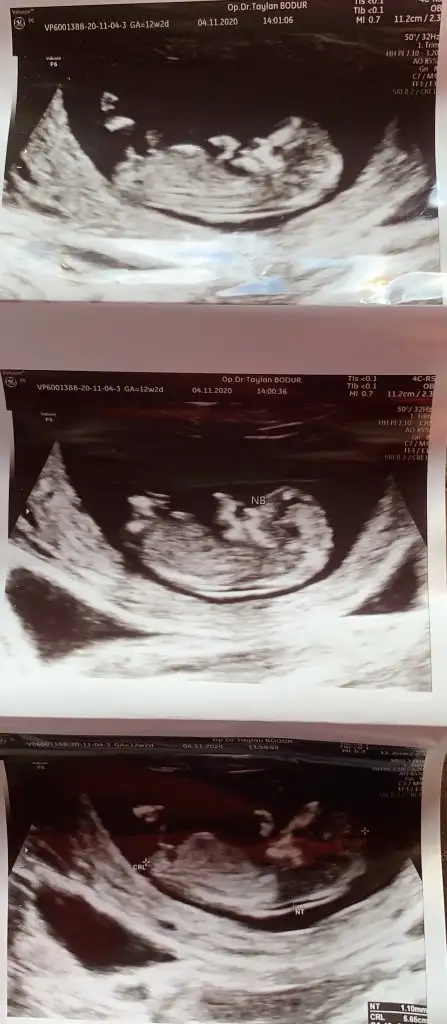

Erkek gibi sankiIkra meyra bize de bakar mısın canım ilki 11+2 diğeri 12+2

Kız gibi sanki net değil birde küçük sanki USG tekrar 11 12 13 haftalar psylasinBakabilir misin canım

Ama ikra meyra kafami karistirdim bana 11 haftada kız dedin bu benimki o daha dikDeğil o kadar belli olmaz daha 11 haftalık

Üste Bak çizdim ve ona kız bebek dedimAma ikra meyra kafami karistirdim bana 11 haftada kız dedin bu benimki o daha dik